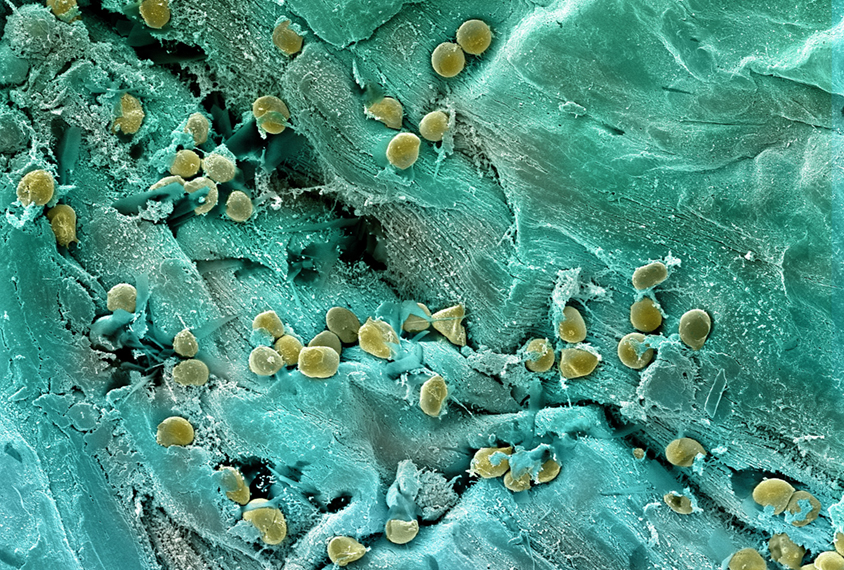

Gut microbiome meta-analysis reveals consistent autism signal

But the field needs to move on from cross-sectional studies to gain insights into the causes and consequences of the association, experts say.

Gut microbiome meta-analysis reveals consistent autism signal

But the field needs to move on from cross-sectional studies to gain insights into the causes and consequences of the association, experts say.